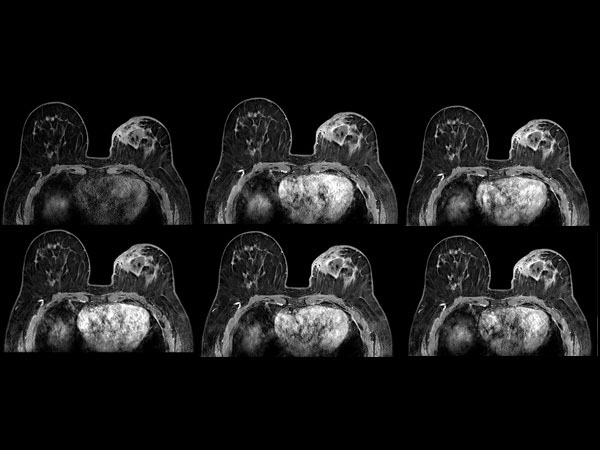

Dynamic axial eTHRIVE

-